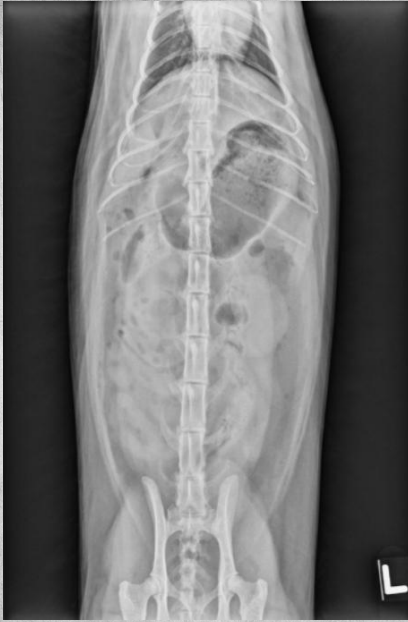

●13 yo female sterilized cat

●Chronic vomiting

● Thin body condition

● Normal serosal detail

● Markedly enlarged small intestinal segment in mid-abdomen containing fluid/soft tissue opacity content with numerous mineral opacity dots.

● Chronic obstruction due to some mass inside small intestine.